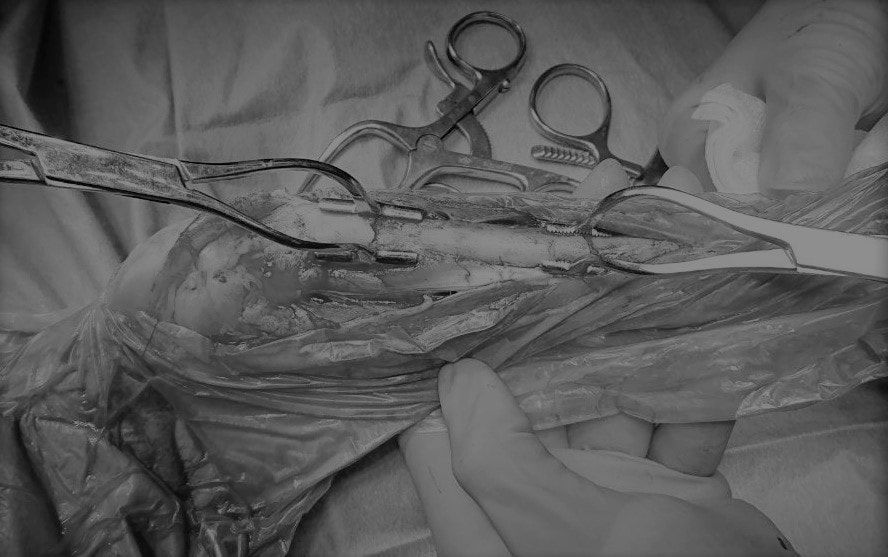

脊髄の減圧、脊柱管の再構築・安定化を目的に、片側椎弓切除術およびMatrixMANDIBLE Plateによる椎体固定を実施しました。

隣接椎体を架橋するようにプレートを設置しました。